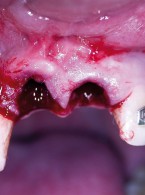

Dekoronacja

jako postępowanie zalecane w leczeniu pacjentów z postępującą pourazową infrapozycją zębów siecznych szczęki